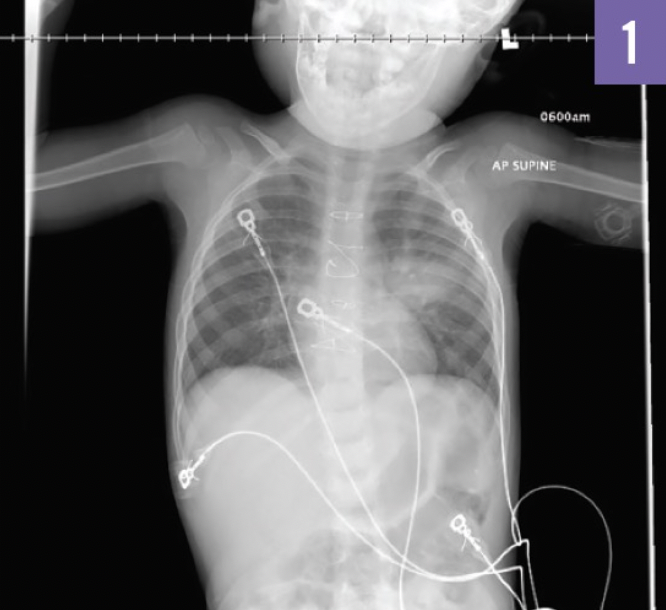

A chest radiograph (Figure 1) demonstrated a single well-circumscribed opacity within the left upper lobe.

Answer: Round pneumonia